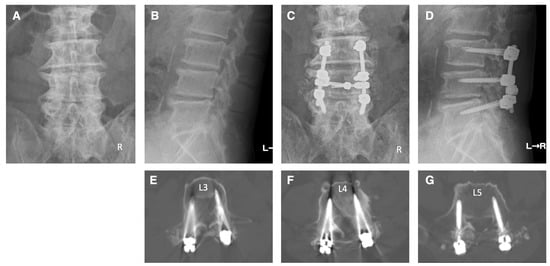

4. Illustrative Cases